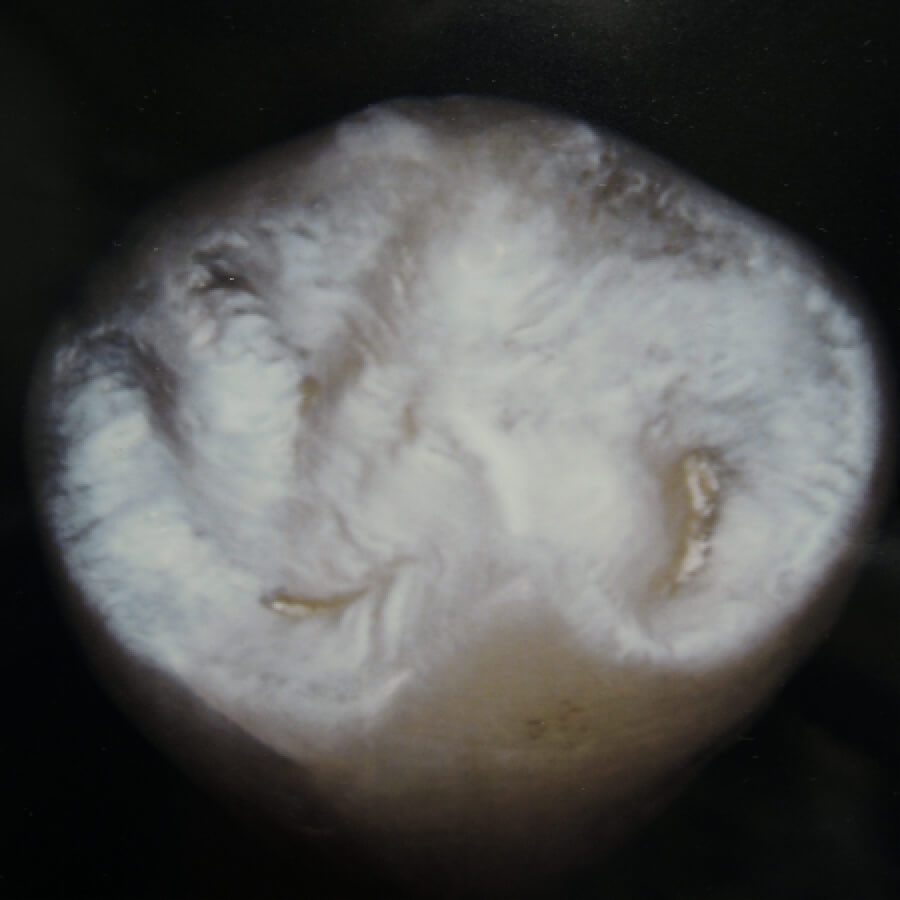

この画像は左は未処理のもの、右は人工エナメル質処理を施した天然歯を撮影したものです。

未処理

小臼歯

大臼歯

人工エナメル質処理

回人工エナメル質処理を行なった歯の画像